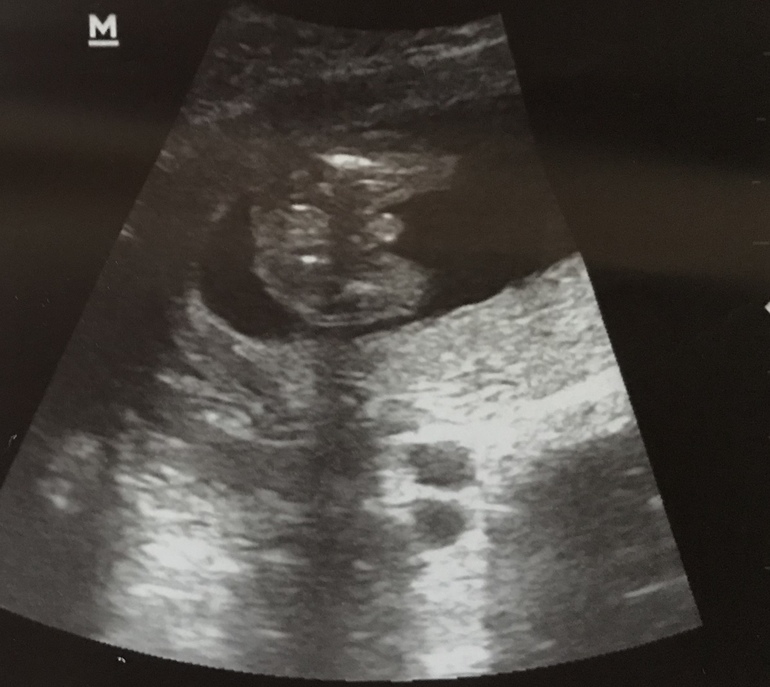

Simerinka в Благополучная беременность 7 лет Пол ребенка Пол малыша Девчат, посмотрите пожалуйста, это мальчик?)) Посмотрите еще 20 записей на эту тему Отменить Ответить Ирчикк А может это пуповина? Подтвердился пол? 03.09.2019 Ответить Simerinka Подтвердился да))) после этого еще было 2 скрининга и одно узи. Сказали хорошо видно, что мальчик 13.09.2019 Ответить Ирчикк Класс. Меняйте кружочек на голубой) Поздравляю! 13.09.2019 Ответить Mila Вне сомнений. Вот это шланг... 17.06.2019 Ответить Кристина Вне всяких сомнений) поздравляю! 30.05.2019 Ответить Маргарита Штольберг Поздравляю с сыночком! А какой у вас срок? 29.05.2019 Ответить Simerinka Спасибо❤️ 17 недель 29.05.2019 Ответить Анна Однозначно) 29.05.2019 Ответить Юлия 💯 пацан😁😁😁 29.05.2019 Ответить Agita Мальчик конечно) 29.05.2019 Ответить nekto Мальчик! По другому быть не может 😅 29.05.2019 Ответить Четырежды мама 😍😍😍 загляденье 🤗🤗🤗 29.05.2019 Ответить Мария Мужичек четкий ) 29.05.2019 Ответить Оставшиеся комментарии доступны после регистрации Зарегистрируйтесь и получите полный доступ ко всем функциям сайта. Зарегистрироваться Пол в 14 недель Первый скрининг пройден Чаты Беременных Выберите чат: Январята-2026 Февралята-2026 Мартята-2026 Апрелята-2026 Майчата-2026 Июнята-2026 Июлята-2026 Августята-2026